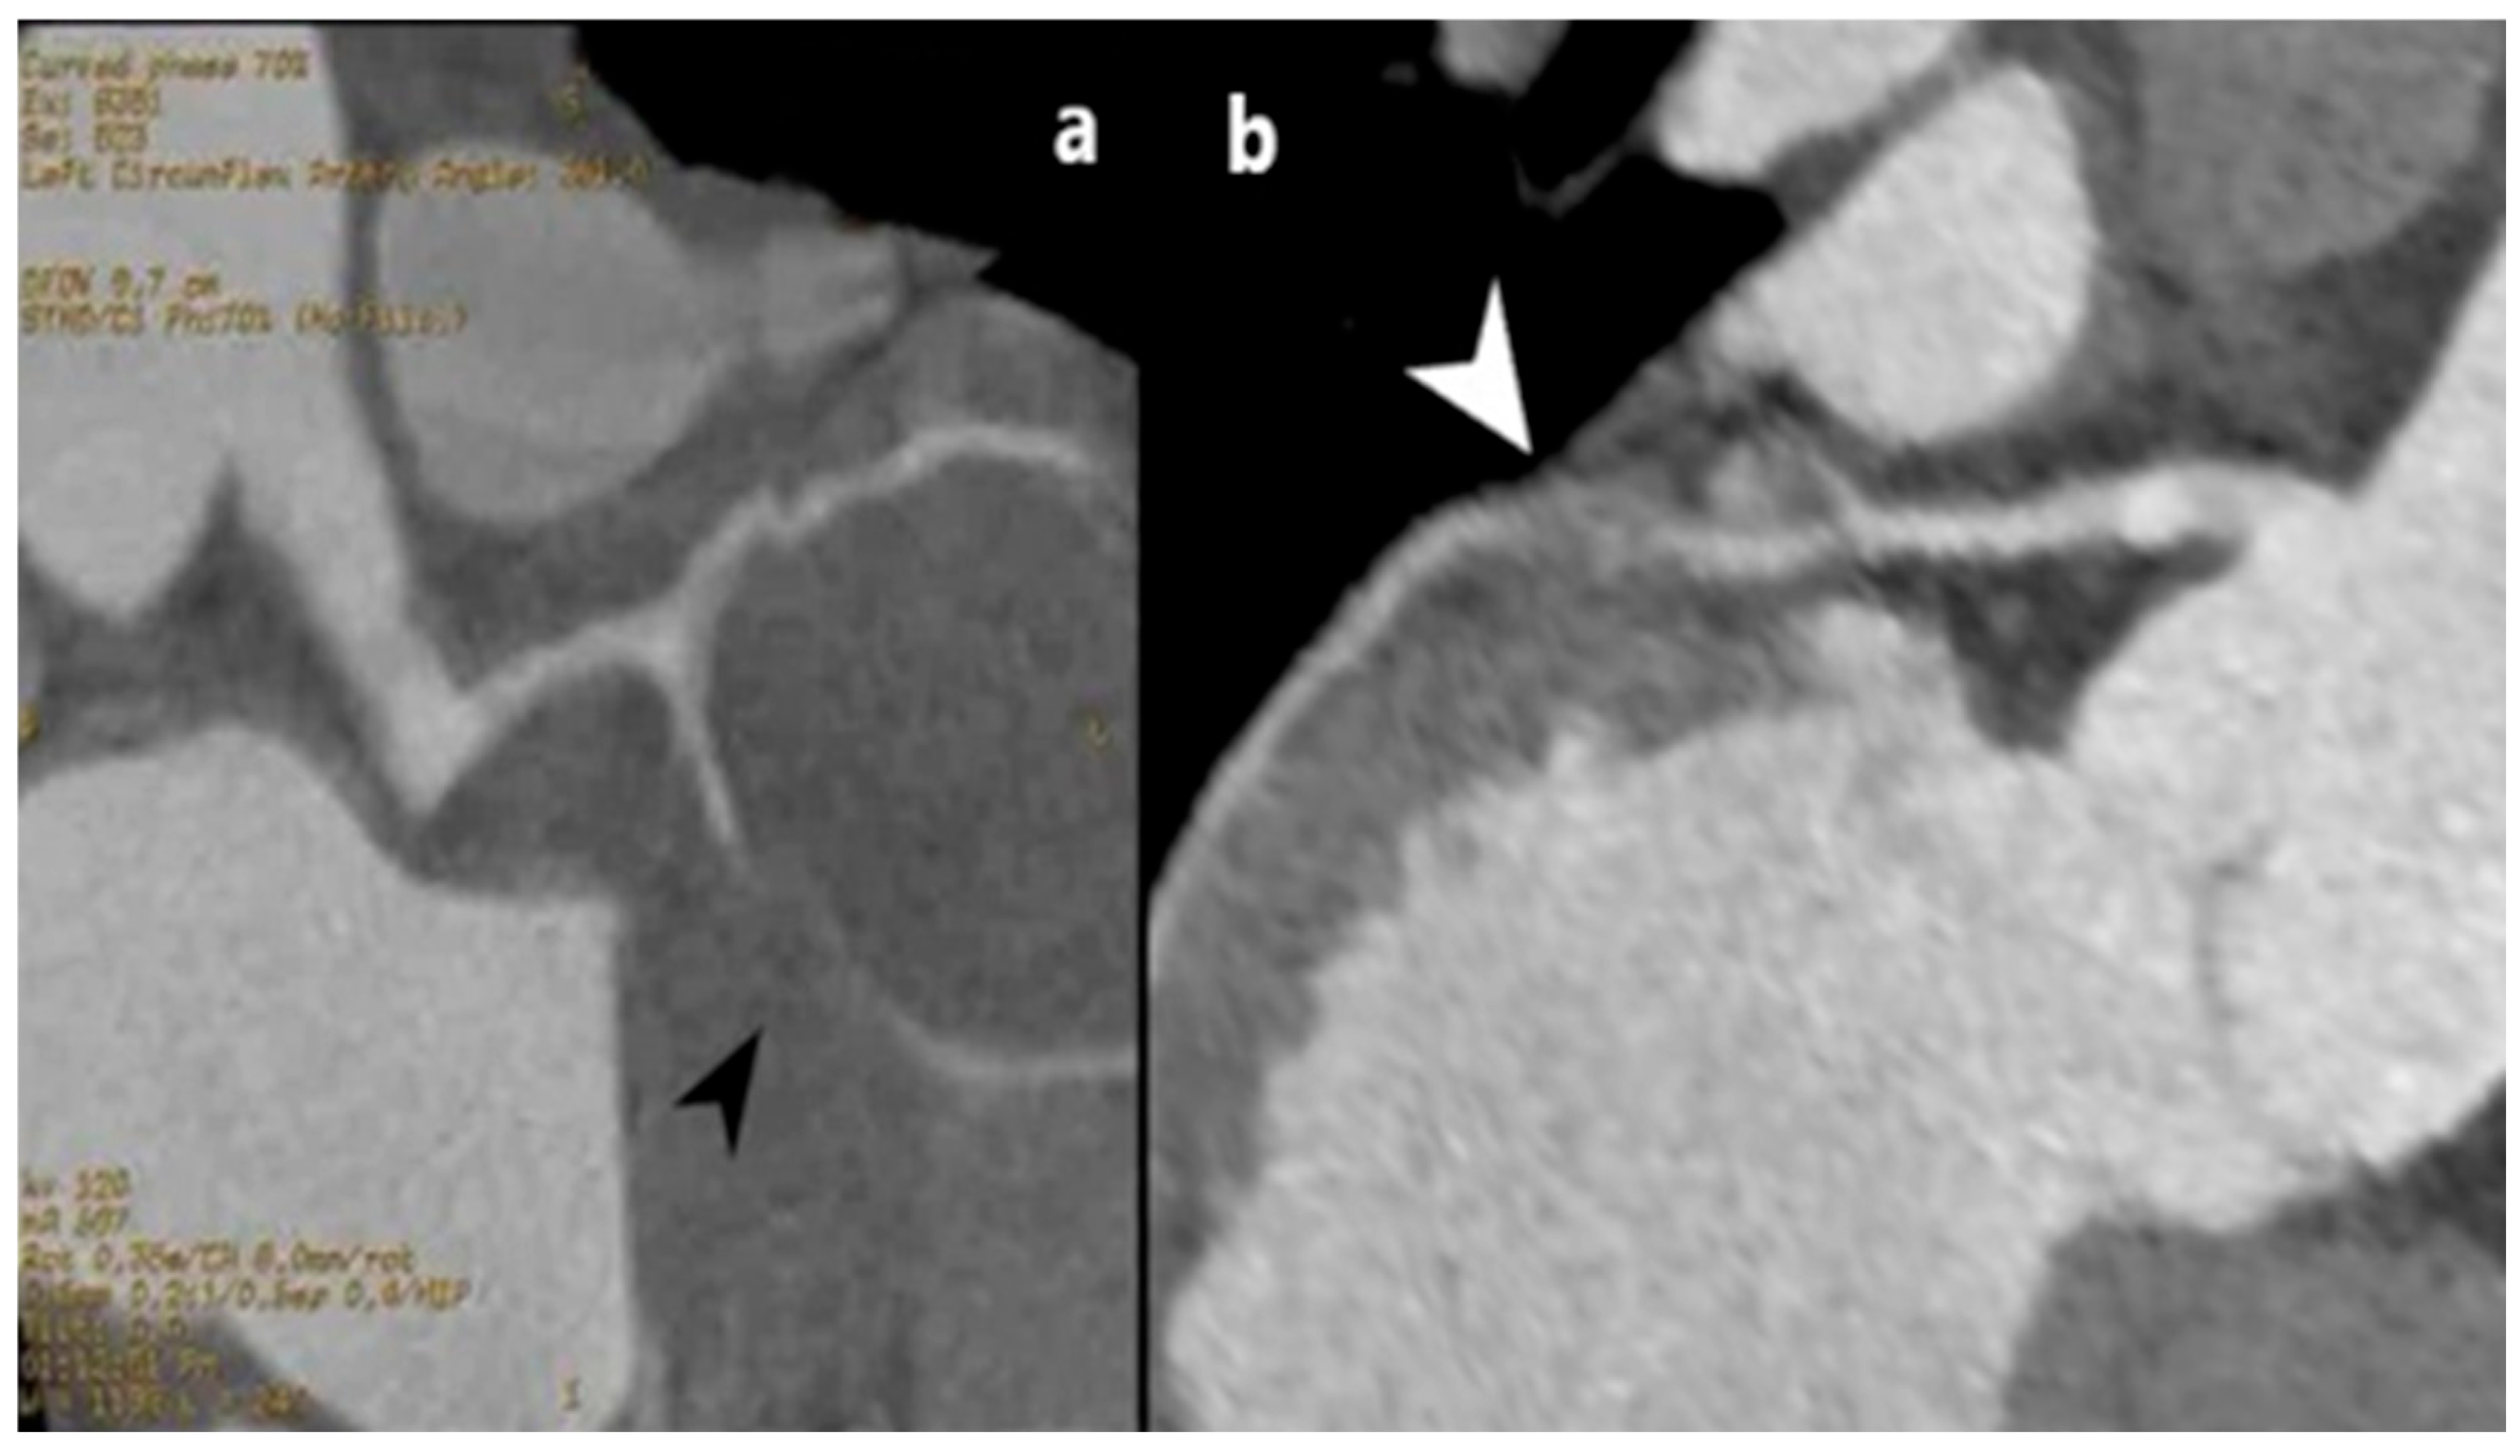

3.1. Myocardial Bridge